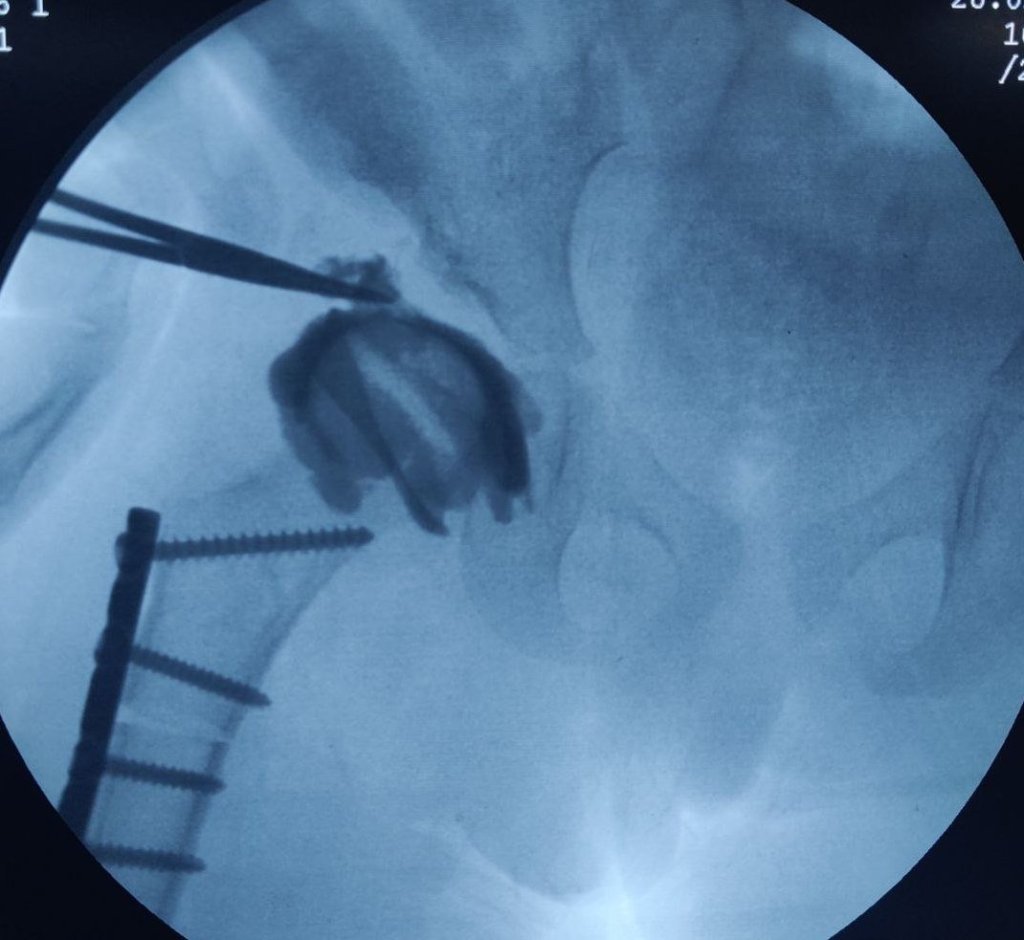

Illustrating below a case whether the Derotation osteotomy was done first and the we decided the acetabular osteotomy based on the cartilage cover on arthrogram.

The Derotation osteotomy improved the coverage but we still have to decide about the acetabular procedure.

An arthrogram reveals a large cartilage cover on superolateral acetabulum. The cartilage bump is pointed to by the forceps.

The C Arm image is superimposed and an artist’s impression is drawn showing what the cartilage would look like in 3D. This offers an excellent teaching tool and a 3D orientation for young surgeons and pediatric orthopedic trainees to decide whether an acetabular osteotomy is needed

The surgeon would then discuss with parents and opt to continue an acetabular procedure of take a staged approach